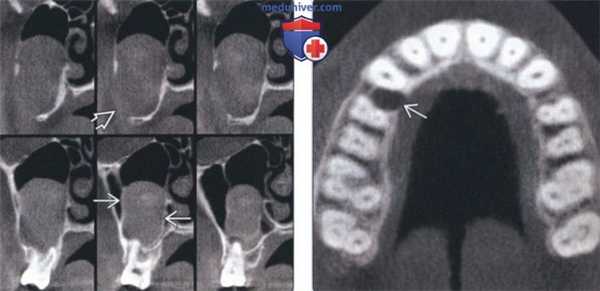

(Слева) На корональныхсрезах (КЛКТ) задних отделов основания черепа у пациента с СБКН в области третьего моляра определяется образование, напоминающее кисту, распространяющееся в верхнечелюстную пазуху. Кортикальная пластинка на периферии означает, что образование возникло за пределами пазухи. Латеральная стенка верхнечелюстной пазухи перфорирована.

(Справа) На аксиальной КЛКТ у этого же пациента определяется маленький формирующийся очаг в верхней челюсти справа. Этот очаг, выявленный случайно, свидетельствует о том, насколько важен анализ данных с целью поиска дополнительных поражений.